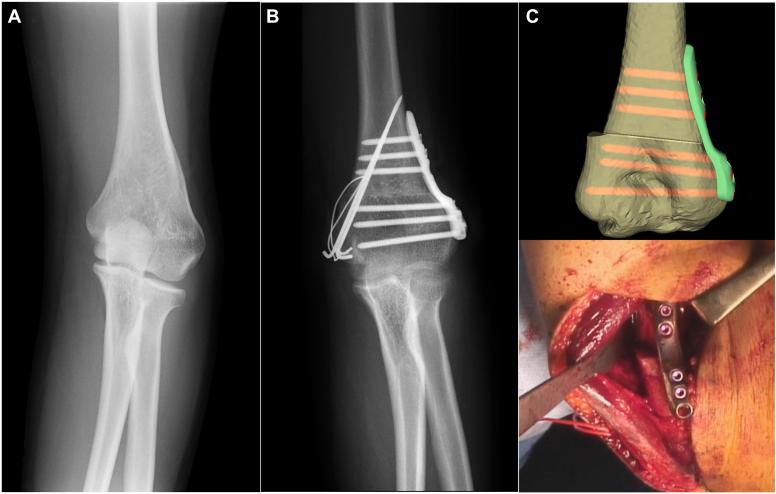

Three-dimensional corrective osteotomy for cubitus varus deformity using patient-matched instruments.

The amount of 3D deformity was calculated based on the difference in 3D shape between the affected side and the contralateral normal side. Patient-matched instruments were created to perform the actual surgery as simulated. Further, a 3D corrective osteotomy was performed using patient-matched instruments for cubitus varus deformity in pediatric and adolescent patients. The humerus-elbow-wrist angle, tilting angle, and elbow ranges of motion were evaluated.

Humerus-elbow-wrist angle and tilting angle were corrected from -21° to 14° and from 30° to 43°, respectively, in the pediatric patient and from -18° to 10° and from 20° to 40°, respectively, in the adolescent patient. The elbow flexion and extension angles changed from 130° to 140° and from 20° to 10°, respectively, in the pediatric patient and from 120° to 130° and from 15° to 0°, respectively, in the adolescent patient.

The 3D computer simulations and the use of patient-matched instruments for cubitus varus deformity are reliable and can facilitate an accurate and safe correction. These technologies can simplify the complexity of 3D surgical procedures and contribute to the standardization of treatment for cubitus varus deformity.